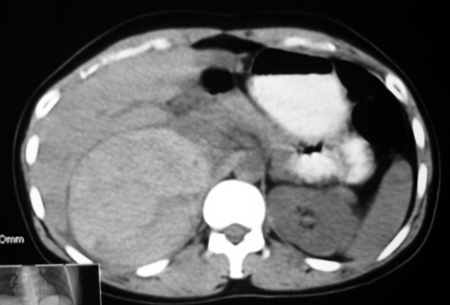

以下是引用卜一在2009-4-23 15:43:00的发言:[br]考虑右肾包膜下血肿,不排除占位病变伴出血可能,建议进一步检查。